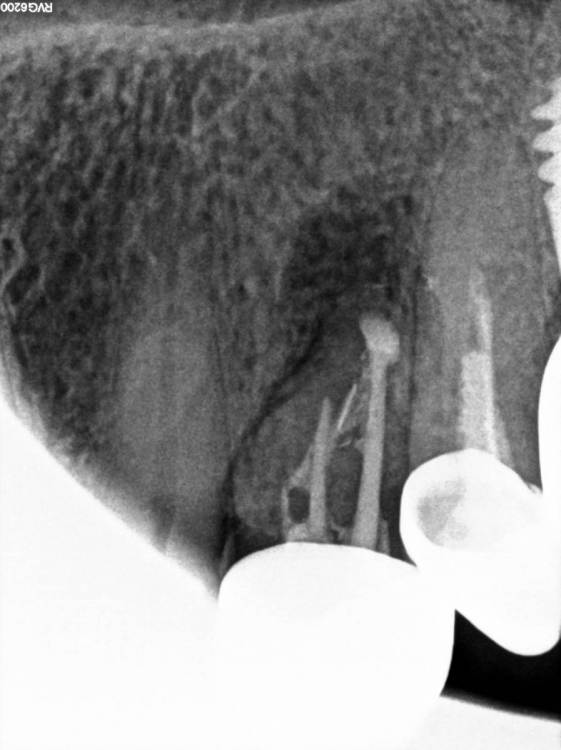

TIGER Опубликовано 29 июля, 2023 Поделиться Опубликовано 29 июля, 2023 (изменено) MAH02590.MP4 Всем привет!Последние лет 5 с внедрением микроскопа в практику стало больше зубо-сохранения,меньше болтов соответственно,что меня радует)Пациент направлен коллегой ввиду невозможности ортоградной ревизии.Проведена зубосохраняющая операция,зуб сохранён.симптомов нет)видео ретро препа тут https://youtu.be/3ukPvjdicW8 MAH02590.MP4 Изменено 29 июля, 2023 пользователем TIGER 3 1 Ссылка на комментарий

TIGER Опубликовано 29 июля, 2023 Автор Поделиться Опубликовано 29 июля, 2023 @Fin спасибо!Канал пломбирую IRM,гемостаз применение артикаина 1:100,капрамин,кости там норм,подвижности нет,плюс сохранения зуба,что организм нам союзник,в отличие от импланта) 1 Ссылка на комментарий